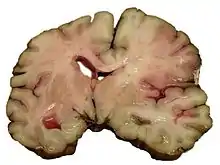

A slice of brain from the autopsy of a person who had an acute middle cerebral artery (MCA) stroke

Strokes can be classified into two major categories: ischemic and hemorrhagic.[18] Ischemic strokes are caused by interruption of the blood supply to the brain, while hemorrhagic strokes result from the rupture of a blood vessel or an abnormal vascular structure. About 87% of strokes are ischemic, the rest being hemorrhagic. Bleeding can develop inside areas of ischemia, a condition known as "hemorrhagic transformation." It is unknown how many hemorrhagic strokes actually start as ischemic strokes.[2]